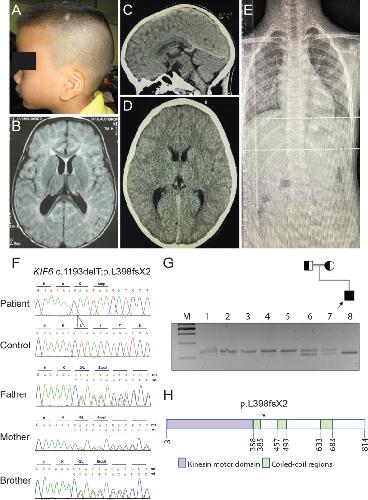

Fig 1. KIF6 mutation in a child with intellectual disability.(A) A low-set prominent anti-helical left pinna. (B) MRI of the brain at 7 months-old shows dolichocephaly with a normal brain structure. (C) and (D) CT of the brain at 8 years-old, sagittal and axial views, respectively show dolichocephalic shape of the cranium (cephalic index = 75) without demonstrable intracranial abnormality. (E) X-ray of the spine shows no scoliosis (F) Electropherograms of the patient, a control, the patient’s father, mother, and unaffected brother from top to bottom. The patient is homozygous for the c.1193delT mutantion while his father, mother, and unaffected brother are all heterozygous carriers. (G) Pedigree and RFLP, using MfeI restriction enzyme: Lane M = 100 bp marker. The arrow head indicates the 500 bp band. Lanes 1–5 are controls. Lanes 6 and 7 are the proband’s father and mother, respectively, showing that they are heterozygous. Lane 8 is the proband showing that he is homozygous for the c.1193delT. (H) Representative KIF6 structure. The arrow shows the position of the c.1193delT mutation.